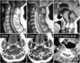

Primary spinal tumor

Spinal tumors are neoplasms located in either the vertebral column or the spinal cord. There are three main types of spinal tumors classified based on their location: extradural and intradural (intradural-intramedullary and intradural-extramedullary). [Source: Wikipedia ]